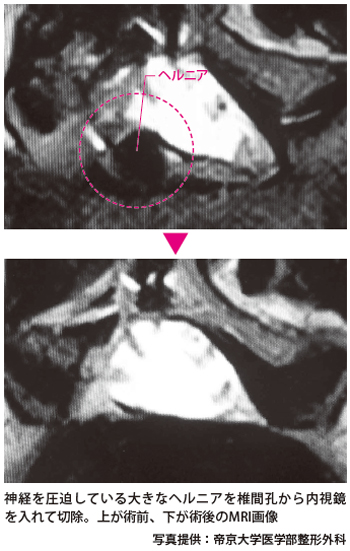

ヘルニアの切除は、内視鏡に設けられている筒状の器具操作用の空間から、手術器具を出し入れして行います。用いるのはボール状のドリルや、切除用の鉗子などで、神経をよけながら、ヘルニアを少しずつ慎重に取り除いていきます。

手術中の圧迫が長いと、神経がダメージを受けてしまうので、手早く行うことがポイントですが、取り残しがあっては手術の意味がなくなります。モニターをよく見て、ヘルニアの取り残しのないようにします。